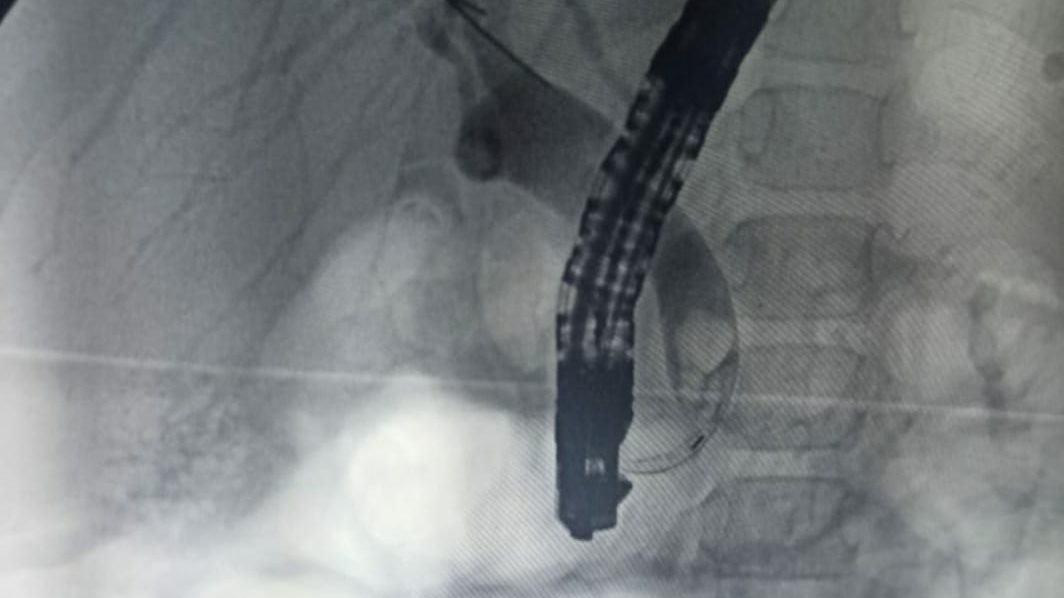

كما يوجد التنظير الصفراوي، حيث يمكن من خلال استخدام كاميرا دقيقة تدخل عبر الفم وتصل إلى القنوات الصفراوية، ويمكن من خلاله تفتيت الحصوات بالليزر وسحبها.